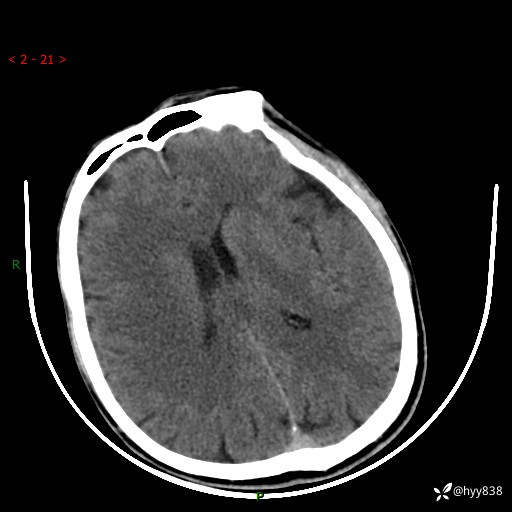

颅脑CT平扫